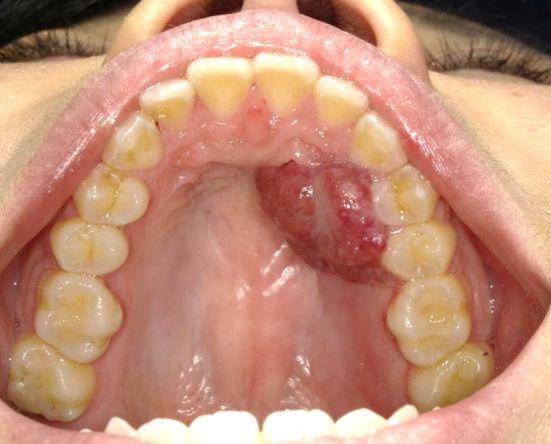

Epulis gravidarum biasanya muncul sebagai benjolan merah muda atau kemerahan pada gusi yang bisa berdarah, baik karena adanya rangsangan maupun secara spontan.

Lesi tersebut mudah berdarah dikarenakan terdapat banyak vaskularisasi atau pembuluh darah. Biasanya epulis gravidarum tidak menyebabkan rasa sakit, tetapi menyebabkan ketidaknyamanan.

Pertumbuhan lesi ini dapat terjadi pada bagian gusi, meskipun sebagian besar terjadi pada mukosa bibir dan pada papilla interdental (gusi pada celah gigi), serta lebih sering terjadi pada rahang atas dibandingkan rahang bawah.

Ukuran tumor atau lesi ini dapat bervariasi, bahkan bisa tumbuh hingga diameter 2 sentimeter (cm). Gigi yang berada di sekitar lesi ini dapat mengalami kegoyahan serta penurunan tulang di sekitar gigi akibat efek kombinasi dari menumpuknya plak gigi pada celah yang terbentuk akibat epulis gravidarum.